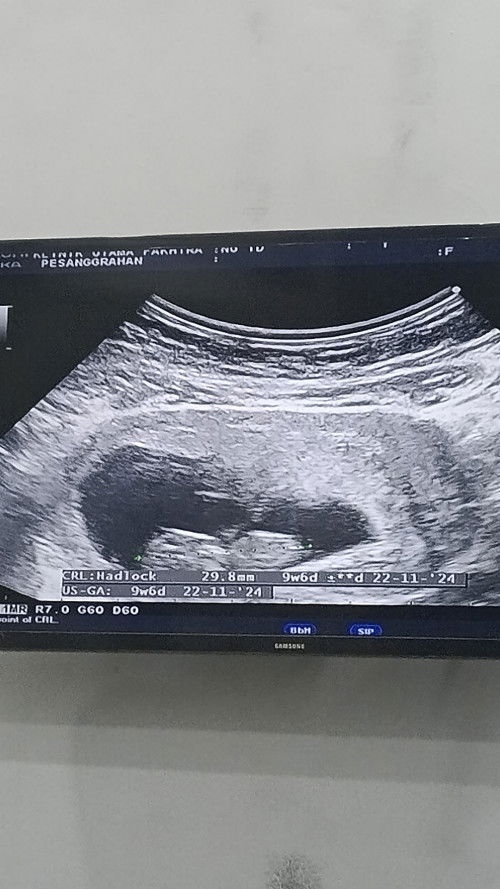

Bun mau tanya aku hamil usia 9mg alhamdulillah udh kedengeran ddj sm janinnya untuk ukuran janin#SeriusTanya 9mmg 29.8mm itu normal kan ya